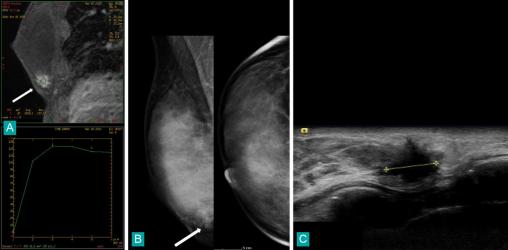

Patiente âgée de 42 ans, porteuse d’une mutation génétique prédisposant au cancer du sein (BRCA1). L'IRM mammaire (fig. A) est réalisée pour le dépistage annuel systématique. Cet examen identifie une masse spiculée rehaussée par le produit de contraste dans la partie profonde et inférieure du sein droit (flèche). La courbe en bas de l'image représente l'évolution au cours du temps de l'intensité du signal au sein de la masse, elle est de type II, en faveur de la malignité. La mammographie réalisée le jour même au décours (fig. B) trouve difficilement cette masse profonde du bord de glande inférieur sur l'incidence oblique (à gauche) [flèche] et ne la retrouve pas sur l'incidence de face en raison de sa profondeur. L'échographie ciblée (fig. C) identifie dans le sillon sous-mammaire droit une masse tissulaire spiculée. La microbiopsie échoguidée a permis le diagnostic de carcinome canalaire infiltrant.